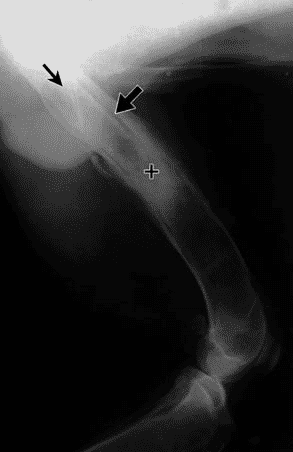

Quand le tissu osseux est infecté il va réagir en produisant du tissu osseux de manière anarchique. A la radiographie, le tissu osseux apparaît irrégulier, flou et mal défini.

En cas de fracture suivie d’une ostéomyélite, le cal osseux est de mauvaise qualité, il est INSTABLE avec des fragments osseux dévascularisés que l’on appelle des « séquestres ».

Ces séquestres sont typiques d’une ostéomyélite.

La petite flèches est un séquestre .

Ces séquestres sont véritablement des supports d’infection et vont contaminer la moelle osseuse de l’os pour aggraver encore plus l’ostéomyélite.

Les signes radiologiques de l’ostéomyélite sont :

présence de « séquestres » : rappelez-vous ce sont ces fameux fragments osseux devascularisés .

Réaction osseuse, opaque aux rayons X, qui entoure les séquestres et que l’on appelle « involucrum » .

Zone de destructions osseuses(Lyse osseuse )

réaction irrégulière du périoste caractéristique (soulèvement du périoste)